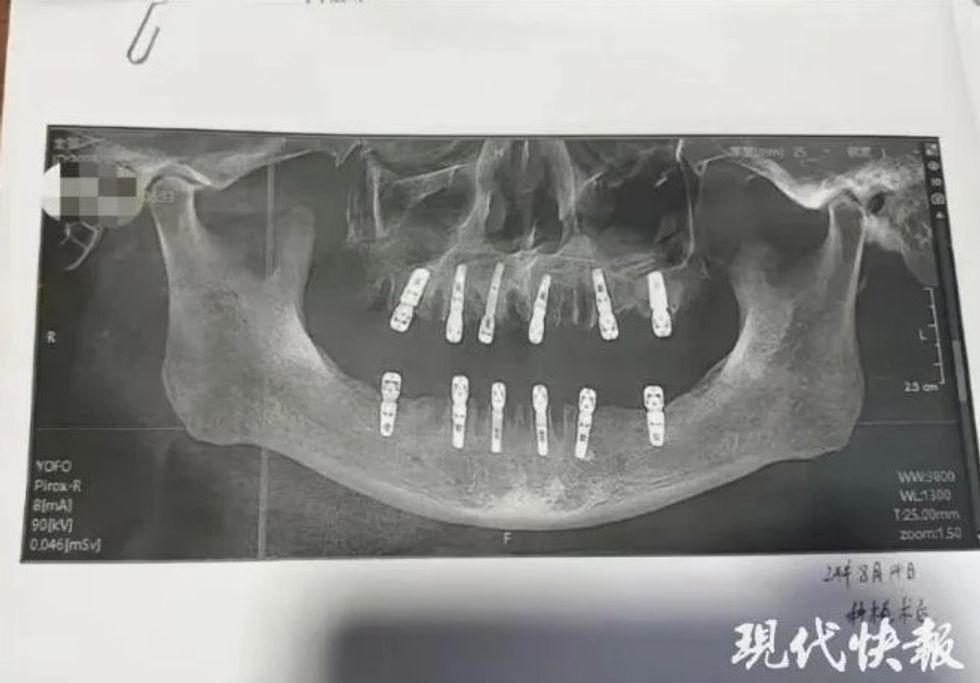

Sipas formularit të pëlqimit të pacientit, babai Shu-s në fakt nxori 23 nga dhëmbët e tij natyralë përpara se t'i hapeshin 12 vrima në kafkën dhe në mandibulën për të vendosur dhëmbë të rinj.

E gjithë kjo u bë në një ditë të vetme, që do të thoshte se ai duhej të duronte dhimbje të paimagjinueshme pasi anestezia mbaroi. Edhe pse numri i nxjerrjeve duket paksa i tepruar për një seancë të vetme, një zëdhënës i klinikës ku është kryer procedura tha se numri i dhëmbëve që mund të hiqen në të njëjtën kohë duhet të përcaktohet nga mjeku personalisht.

Sipas të dhënave të Spitalit Dental Dewei, 23 nxjerrjet u kryen nga një mjek i quajtur Yuan, specialitetet e të cilit përfshijnë trajtimin e kanalit të rrënjës, heqjen e dhëmbëve dhe protezat e plota. Megjithëse aktualisht nuk ka një rregullore specifike për numrin e dhëmbëve që duhen nxjerrë në një seancë të vetme, klinika dhe mjeku duhet të marrin parasysh tolerancën ndaj dhimbjes së pacientit dhe rrezikun e infeksionit.